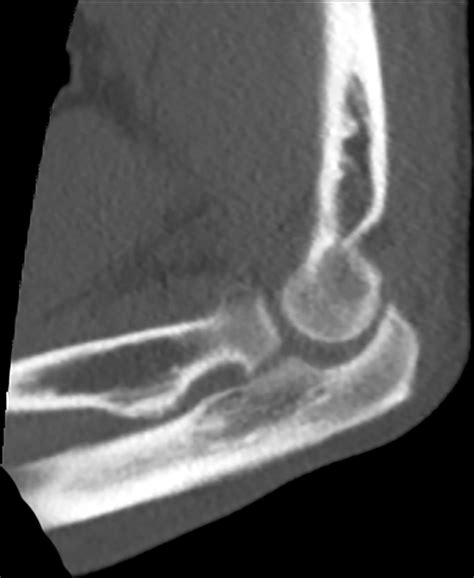

• Fractures: This is the most common reason. It can range from obvious, displaced fractures to subtle hairline or stress fractures that are difficult to visualize without advanced imaging.

CT Scan Very High Provides detailed, cross-sectional views; excellent for complex fractures.

• acute osseous abnormality knee